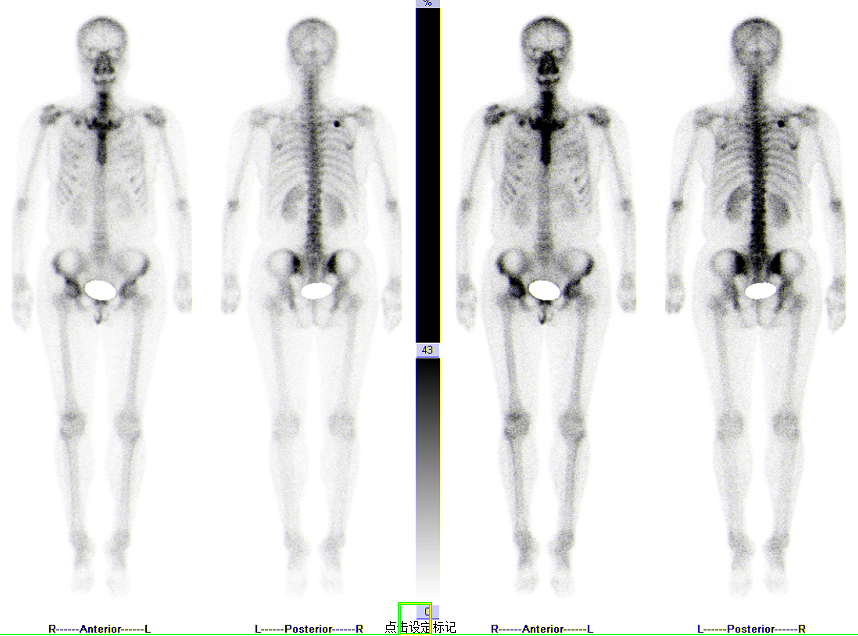

三、两者综合应用

通过对以上内容的了解,我们可以得知全身骨显像虽然可以观察骨质结构的变化,但如同盲人摸象,没有局部影像对病灶部位的指示,诊断结果仍然受限,而脏器断层显像不是单纯的SPECT影像和CT影像,而是两者功能的融合影像。并且,大部分病灶的发生发展是先有骨质代谢的异常,再出现CT能看到结构异常,SPECT能较CT早发现病灶2-3个月。反之,局部脏器断层显像的检查范围有限,不如全身骨显像广泛,仅依靠骨痛主诉进行区域检查很容易漏诊病灶。所以,在临床应用中,医生时常会建议患者在行全身骨显像检查后进行脏器断层显像检查,而后结合二者影像结果对病症进行综合判断。

如图所示,胃恶性肿瘤患者,全身骨扫描显示:右侧第6腋肋放射性摄取增高,左侧第3-6前肋放射性摄取增高。进一步加做胸廓断层显像(SPECT/CT)后,影像显示右侧第6腋肋局部放射性摄取增高灶,肋骨骨密度增高,诊断为骨转移;左侧第3-6前肋放射性摄取增高,局部骨皮质皱褶,欠连续,诊断为陈旧性骨折。